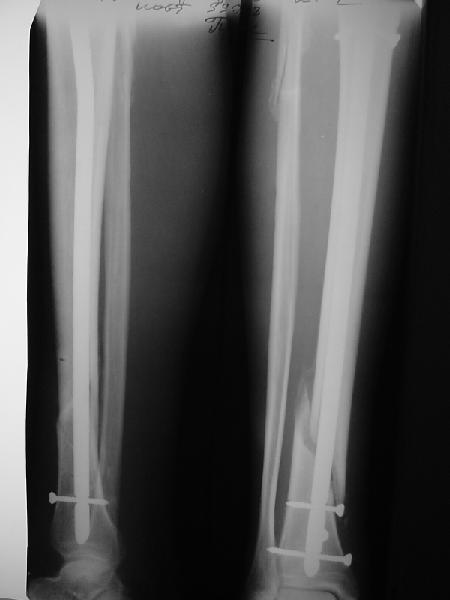

Ok. А также и следующий, в 3 месяца.

Это наглядная демонстрация возможности ранней полной нагрузки при нестабильном по оси повреждении, причем не в самых благоприятных механических условиях - при плохом сопоставлении, со слабым фиксатором.

Как я уже говорил, мы сделали выводы из этого и других подобных случаев. Очевидно, решений проблемы два - либо уменьшить нагрузку, либо увеличить прочность фиксатора. Первое решение работает не со всеми больными, так что пошли по второму пути - мы больше не используем гвозди с запирающими винтами диаметром 4 мм.